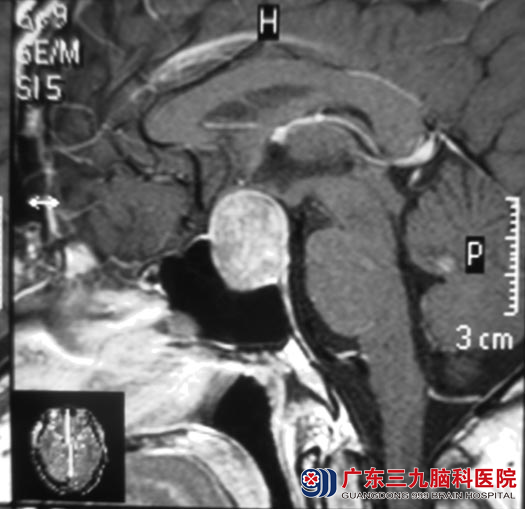

手术前